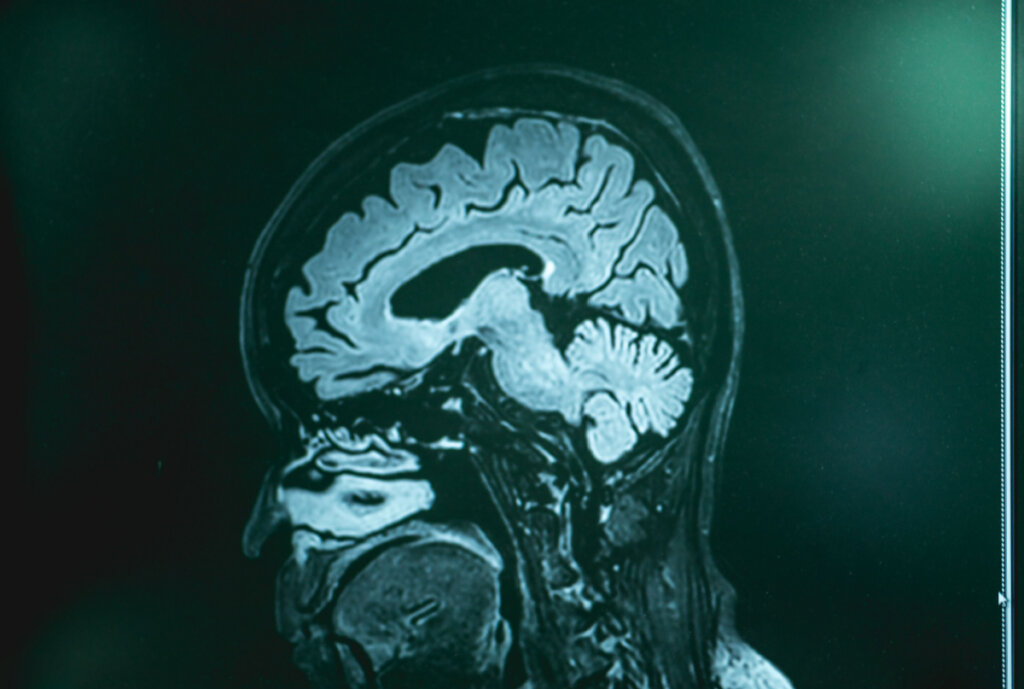

Huolimatta siitä, että tämäntyyppisen dementian syy-seuraus -suhteesta ollaan melko tietämättömiä, useita hypoteeseja on harkittu, joista osa on menestyneempiä kuin toiset. Neurokuvausmenetelmien avulla näillä potilailla voidaan havaita tiettyä atrofiaa. Toisin sanoen aivokuoren tiettyjen alueiden, erityisesti ohimolohkon ja otsalohkon, kutistumista.